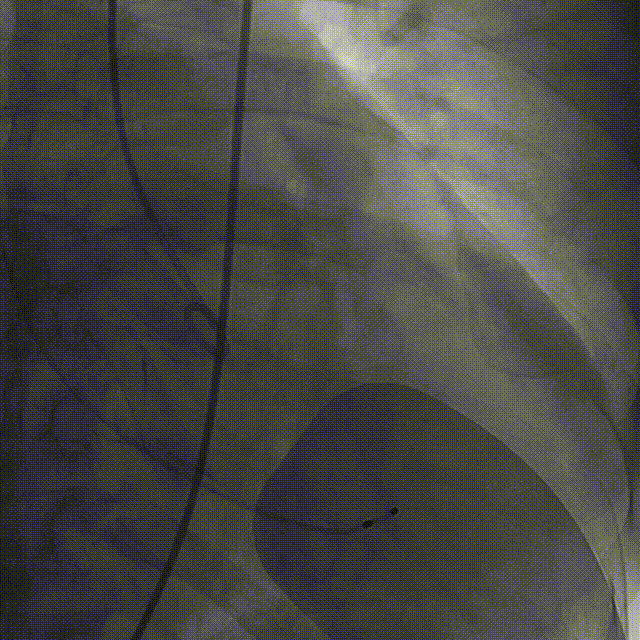

术前右窦中心造影

大鞘植入